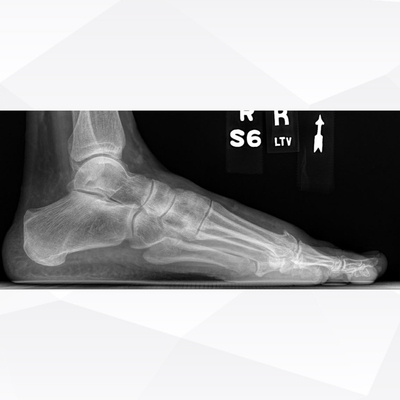

Click on an image below to view more info.